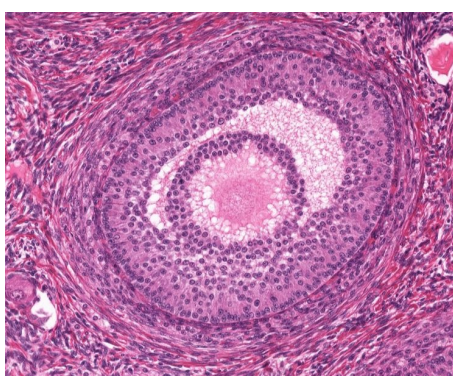

red

granulosa cells

orange

thecal cells

yellow

zona pellucida

What is this

secondary follicle